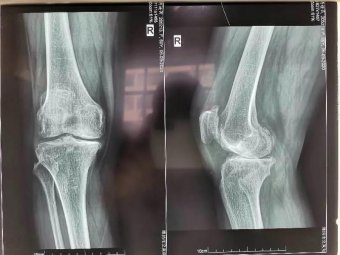

精于微創(chuàng)|山醫(yī)集團(tuán)濰坊市市立醫(yī)院骨二科成功開展全膝關(guān)節(jié)置換術(shù) 日期:2020-09-22 11:35:21 點(diǎn)擊:2323 好評(píng):48

今年60歲的考大姨,飽受膝關(guān)節(jié)疼痛之苦長(zhǎng)達(dá)8年,她曾四處求醫(yī),接受各種保守治療,至今跛行,且癥狀逐年加劇。近日因右膝疼痛加劇、腫脹,行走200米便無(wú)法繼續(xù)行走,嚴(yán)重影響日常生活,被親友急送濰坊市市立...